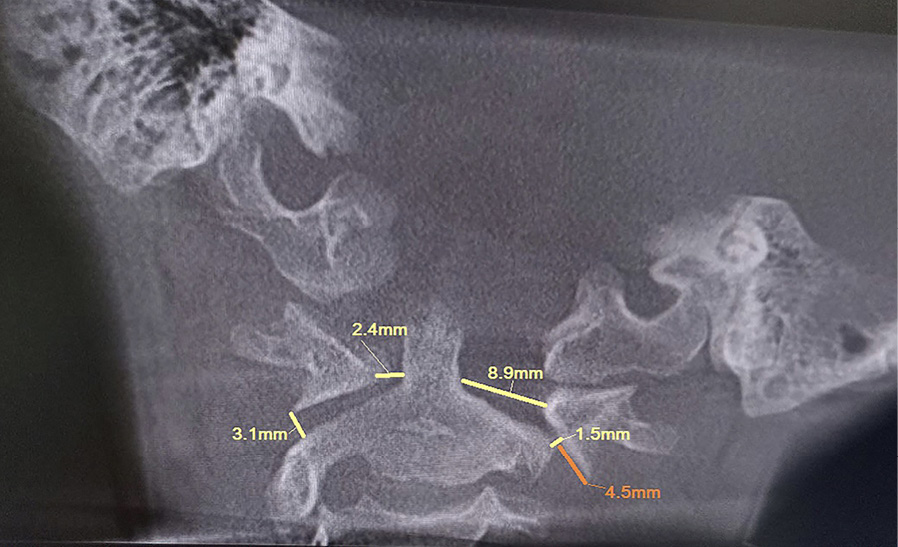

Для уточнения характера выявленных изменений в ручном режиме с помощью программы Adobe Photoshop© выполнено наложение аксиальных срезов 1-го и 2-го шейных позвонков, полученных по отдельности, с созданием единого изображения с возможностью комплексной оценки взаимоотношений изучаемых сегментов (рис. 2). При анализе смоделированного изображения обнаружено, что ротация атланта составляет 35° вправо (рис. 3). Суставные поверхности латерального атлантоаксиального сустава справа совпадают, а слева –суставная поверхность атланта смещена кпереди, что соответствует ротационному подвывиху типа II по классификации J. W. Fielding и R. J. Hawkins [8].

Рис. 2. Конусно-лучевая компьютерная томография краниовертебральной области. Аксиальные срезы на уровне аксиса (А) и на уровне атланта (Б). Стрелками обозначены передне-задние оси позвонков

Рис. 3. Наложение изображений А и Б, представленных на рис. 2. Определение угла ротации атланта